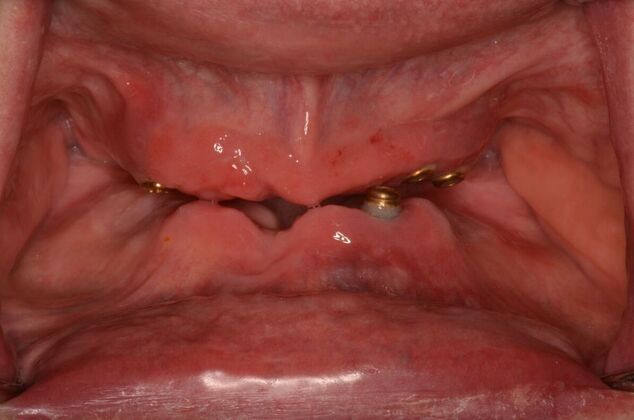

This busy professional unfortunately had lost all his teeth and then had implants placed for snap on dentures. The implants started failing after a few years and experienced bone loss. Patient was previously told my multiple dentists that he was not a candidate for dental implants. Patient was always unhappy with his snap on dentures and desired a permanent solution. The old implants were removed and Dr Bidra placed new implants in the upper and lower jaw and installed permanent teeth in the same day. After 4 months of healing, new zirconia permanent teeth were installed.

Procedures : extractions, failing snap on dentures, new implants, All on 4 , Teeth in a day, no bone grafting and full mouth reconstruction with monolithic zirconia bridges.